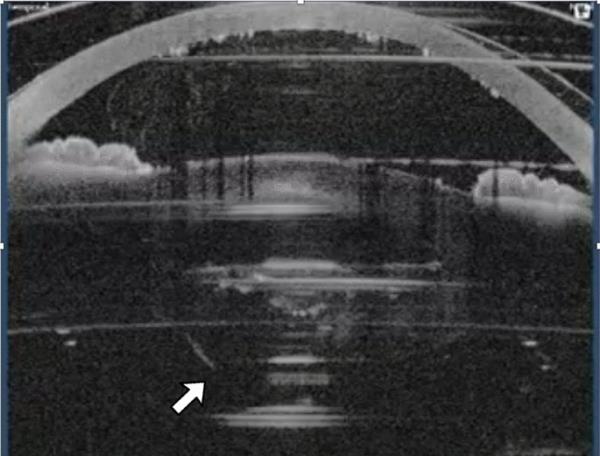

一位58岁的男性患者在第一只眼白内障手术成功后,又来做第二只眼白内障手术。眼部结扎和囊膜切开术无大碍。在囊膜切开后,激光技师注意到眼睛有一些运动,并建议外科医生停止手术(图1)。外科医生决定继续手术,但在手术过程中,在下周后囊发现了部分切口。摘除白内障,在睫状沟植入3片人工晶状体。后来,视网膜脱离,需要两次进一步的手术。截至2年后的最近一次就诊,视网膜附有0.1 LogMAR矫正视力。

图1

囊膜切开后眼倾斜,此时碎片量已经设定。这导致后囊部分被飞秒激光切割